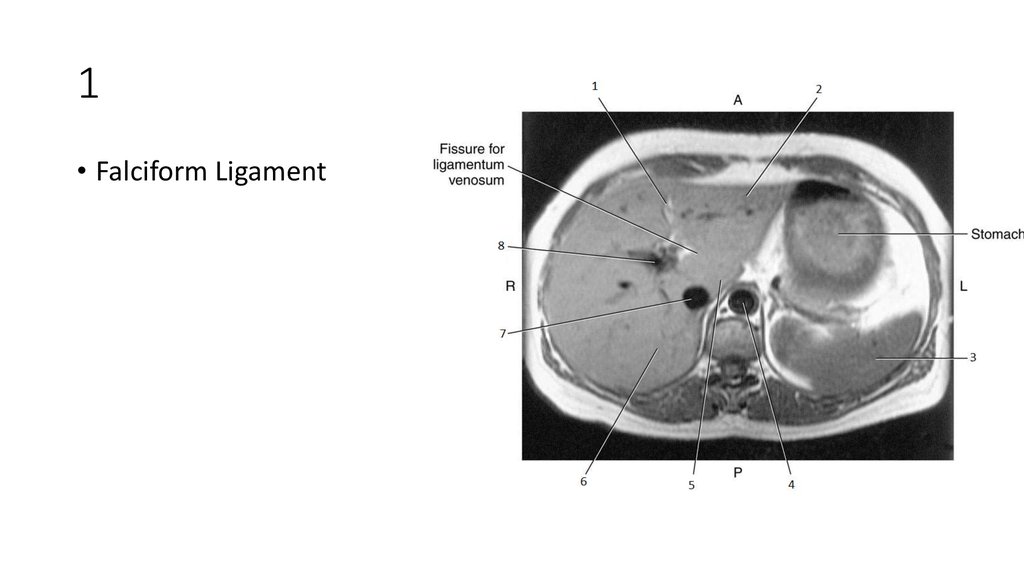

16. 1

17. 1

• Falciform Ligament

18. 2

19. 2

• Left lobe of Liver

20. 3

21. 3

• Spleen

22. 4

23. 4

• Aorta

24. 5

25. 5

• Caudate Lobe of Liver

26. 6

27. 6

• Right Lobe of Liver

28. 7

29. 7

• Inferior Vena Cava (IVC)

30. 8

31. 8

• Portal Vein